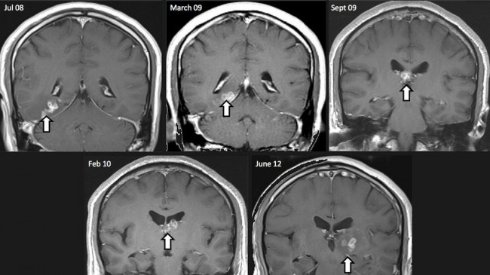

Один из таких червей пробрался в

После операции по извлечению червя из